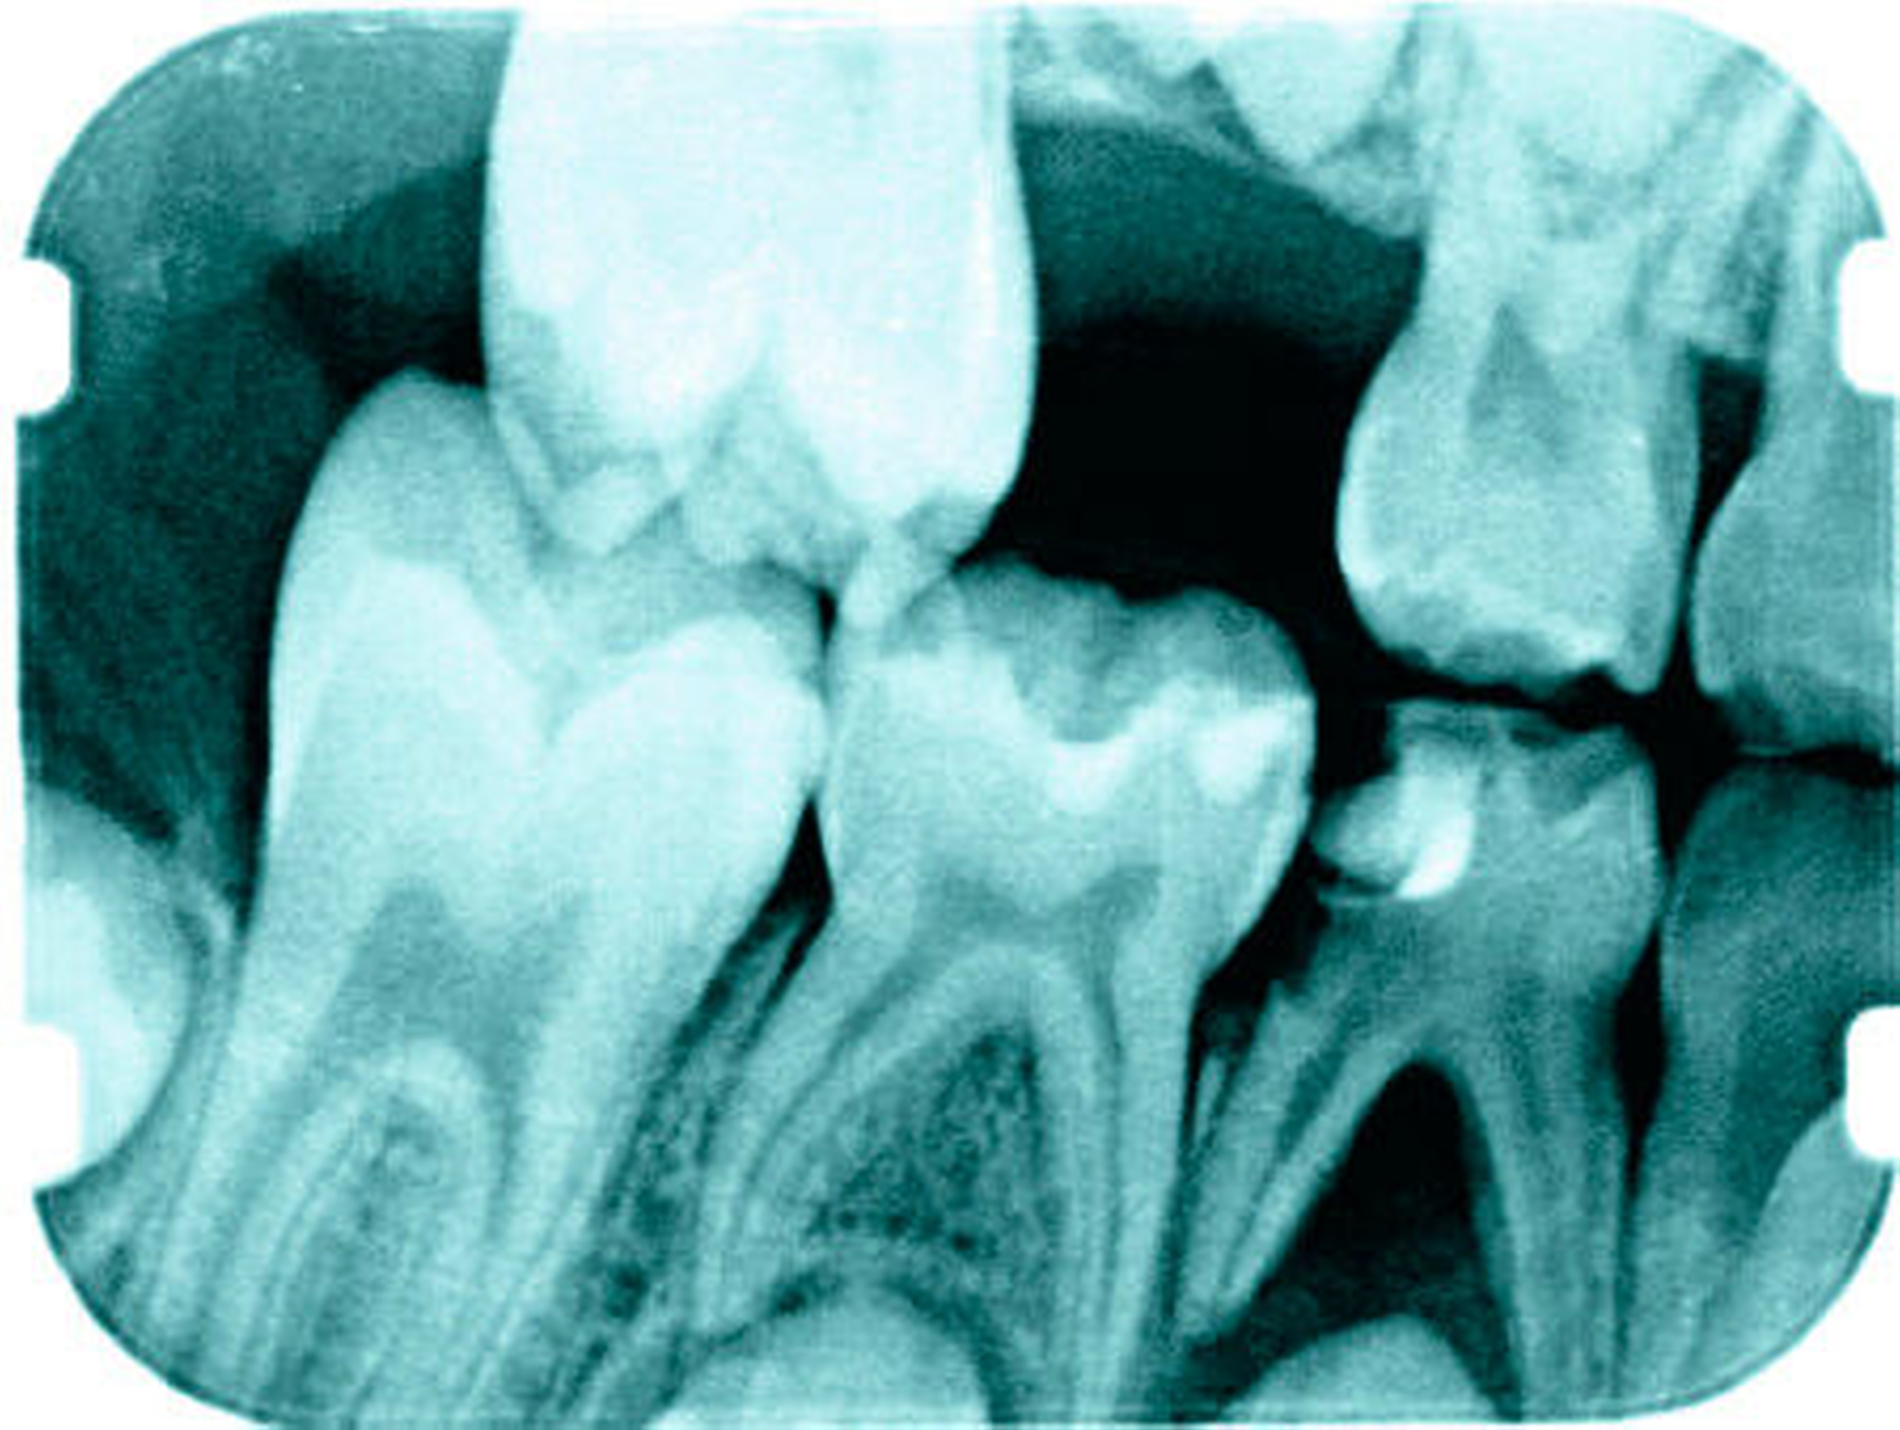

Für die Therapie im Milchgebiss ist eine exakte Diagnosestellung anhand eines röntgenologischen und klinischen Befunds essenziell. Es sollte an dieser Stelle erwähnt werden, dass sich die Mikrostruktur des Milchzahns aufgrund pulpanah vergrößerter Dentintubuli prägnant von der des bleibenden Zahnes unterscheidet. Dieser Aspekt beeinflusst die Wahl der Therapie und führt allgemein zu einer rascheren Progression der – besonders approximalen – kariösen Läsion bis hin zur Infektion des pulpalen Gewebes [Angker et al., 2003; Kassa et al., 2009]. Bei vorangegangener apikaler Inflammation, Fistelbildung oder Abszedierung ist eine Extraktion angezeigt (Abbildung 3).

Approximalkaries oder gar fehlende Milchmolaren bedingen eine Mesialwanderung der benachbarten Molaren, es kommt zu einem Stützzoneneinbruch (Abbildung 5) mit Platzdefizit in der Sagittalebene. Durch den Verlust der sagittalen Milchzahndimension aufgrund von Approximalkaries oder gar fehlender Zähne kann es zu einem sekundären Engstand kommen. Daher sollte penibel darauf geachtet werden, durch geeignete konservierende Maßnahmen (approximal konvex gestaltete Füllungen oder pädiatrische Kronen, Abbildung 6), die physiologische Dimension des Milchzahns zu erhalten [Krämer et al., 2010]. Ein Mesialdrift des zweiten Milchmolaren oder des ersten bleibenden Molaren sollte unbedingt vermieden werden.